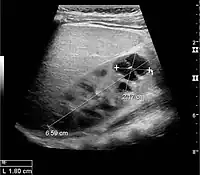

Figure 8. Cortical solid mass, which later was shown to be renal cell carcinoma. Measurement of the solid mass on the US image is illustrated by '+' and a dashed line.[1]

Figure 9. Renal cell carcinoma with both cystic and solid components located in the cortex. Measurement of tumor on the US image is illustrated by '+' and a dashed line.[1]

A solid renal mass appears in the US exam with internal echoes, without the well-defined, smooth walls seen in cysts, often with Doppler signal, and is frequently malignant or has a high malignant potential. The most common malignant renal parenchymal tumor is renal cell carcinoma (RCC), which accounts for 86% of the malignancies in the kidney. RCCs are typically isoechoic and peripherally located in the parenchyma, but can be both hypo- and hyper-echoic and are found centrally in medulla or sinus. The lesions can be multifocal and have cystic elements due to necrosis, calcifications and be multifocal (Figure 8 and Figure 9). RCC is associated with von Hippel–Lindau disease, and with tuberous sclerosis, and US has been recommended as a tool for assessment and follow-up of renal masses in these patients.[1]

However, US is not the primary modality for the evaluation of solid tumors in the kidney, and CT is the first choice modality. Nevertheless, hemorrhagic cysts can resemble RCC on CT, but they are easily distinguished with Doppler ultrasonography. In RCCs, Doppler US often shows vessels with high velocities caused by neovascularization and arteriovenous shunting. Some RCCs are hypovascular and not distinguishable with Doppler US. Therefore, renal tumors without a Doppler signal, which are not obvious simple cysts on US and CT, should be further investigated with CEUS, as CEUS is more sensitive than both Doppler US and CT for the detection of hypovascular tumors.[1]